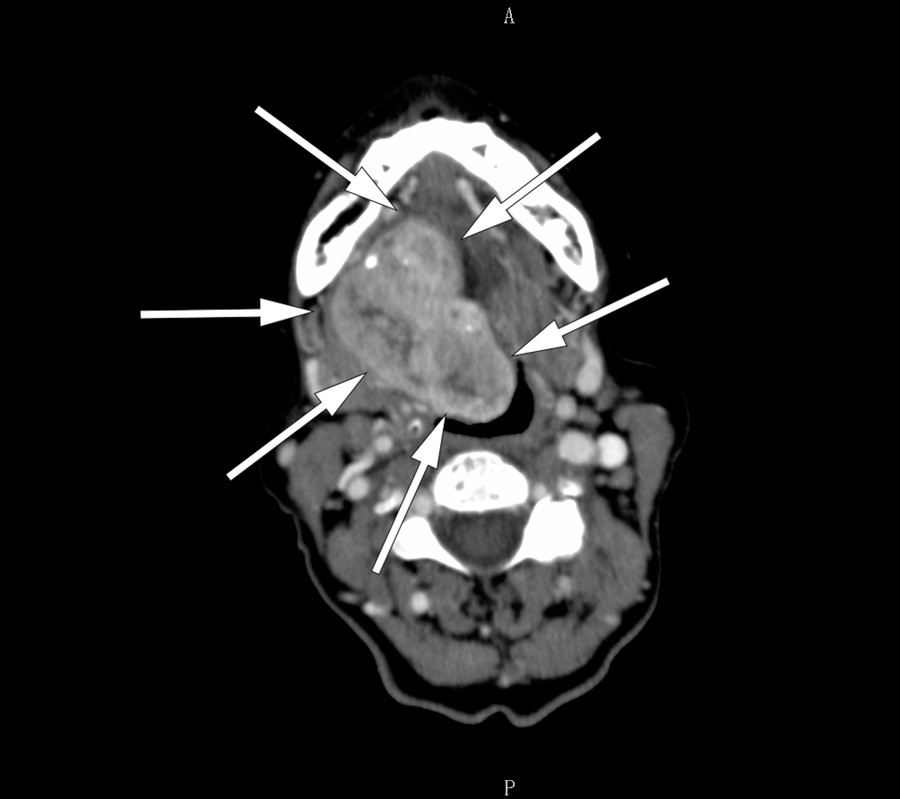

Det ble tatt CT collum med kontrast (bilde til venstre), som viste en stor tumor i munngulvet. MR collum med kontrast (bilde til høyre) viste uregelmessig kontrastopptak i tumor. Finnålscytologi viste vev best forenlig med glandula thyreoidea uten tegn til malignitet. Funnene tydet på ektopisk thyreoidea, og regranskning av CT-bildene viste manglende thyreoideavev på vanlig lokalisasjon. Blodprøver viste at pasienten var eutyreot og negativ for antityreoperoksidase og antityreoglobulin.